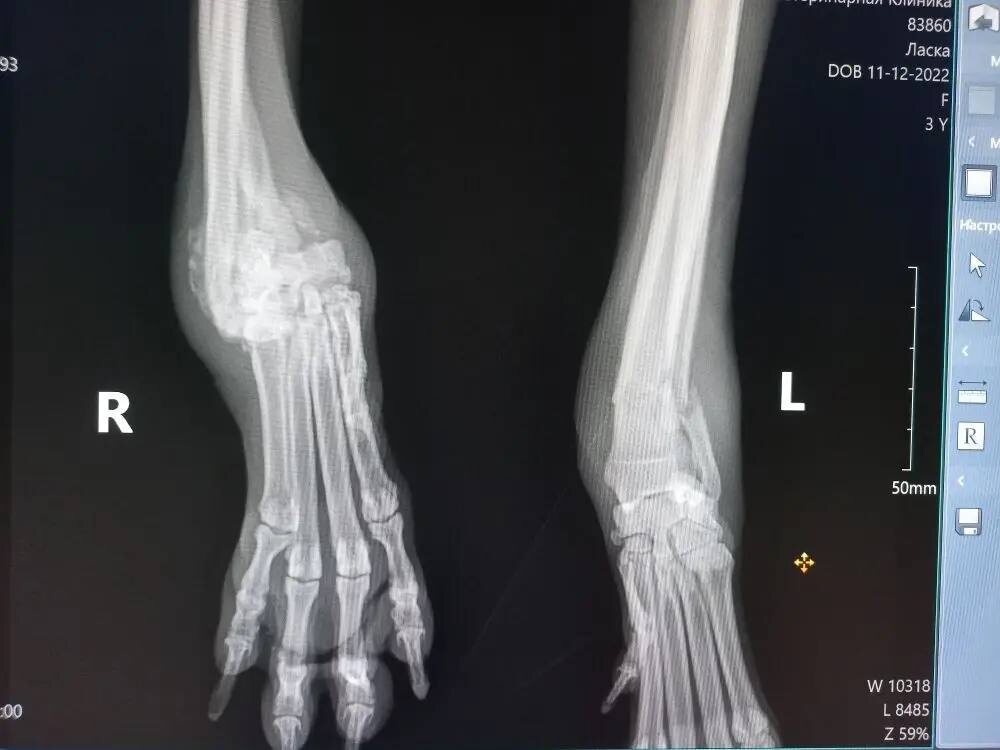

У Ласки застарелый перелом одной лапы. На второй лапе перелом свежий, воспаление, болезненный отек.

В понедельник нужно везти на операцию.